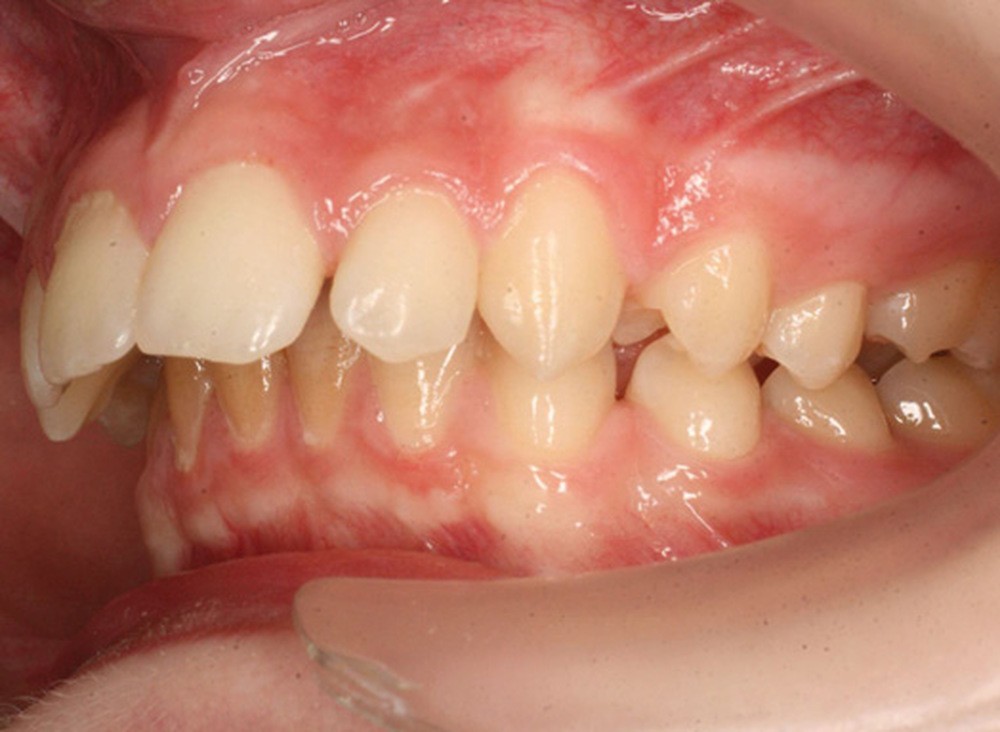

Y a-t-il plus grave échec que de terminer un traitement à l’adolescence en classe II molaire et canine ?

La sanction est systématique à moyen terme avec récidive de la supraclusion et de l’encombrement maxillaire. Le retraitement est complexe et nécessite souvent chez le patient une fois à l’âge adulte :